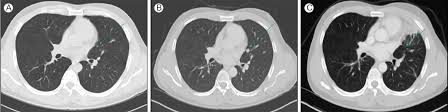

- 흉부 X‑선 또는 흉부 CT로 발견

- 이전 영상과 비교하여 결절의 변화 여부 확인

- 결절 크기·형태·경계·석회화 여부 등 특징 분석

- 의심되는 경우 PET-CT 스캔 또는 조직 생검 시행